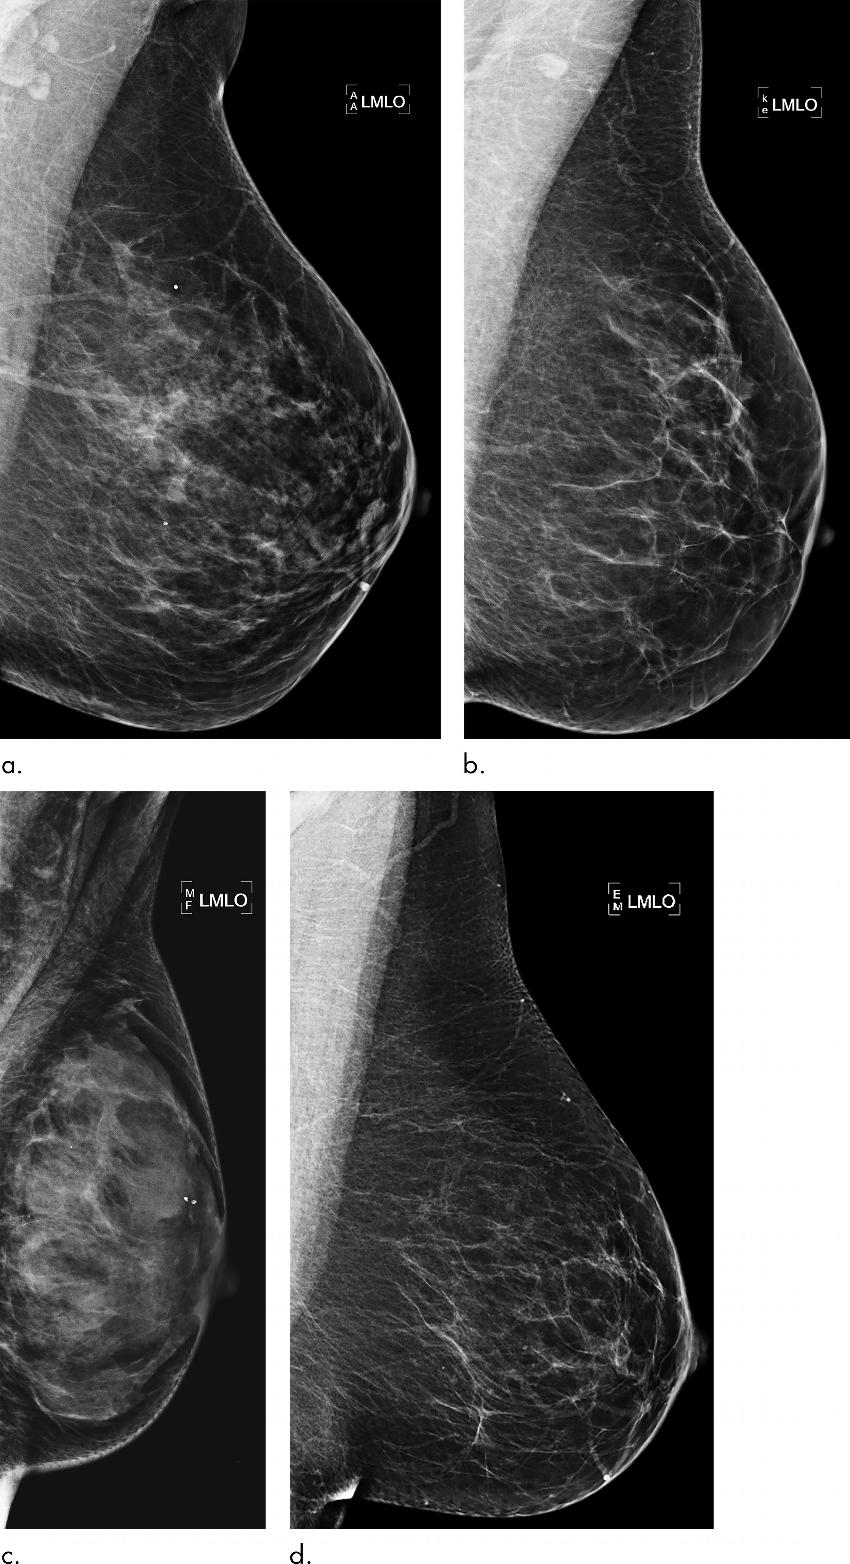

Figure 3. : Examples of mammograms with discordance between deep learning (DL) risk score and outcome of breast cancer (false predictions). All images are mediolateral oblique views of left breast. (a) Mammogram in 44-year-old woman with low DL risk score (0.05) who received a diagnosis of breast cancer 4.7 years after the examination (ie, false-negative prediction). (b) Mammogram in 40-year-old woman with low DL risk score (0.07) who received a diagnosis of breast cancer 4.1 years after the examination (ie, false-negative prediction). (c) Mammogram in 65-year-old woman with high DL risk score (0.53) who was not diagnosed with breast cancer (ie, false-positive prediction). (d) Mammogram in 65-year-old woman with high DL risk score (0.48) who was not diagnosed with breast cancer (ie, false-positive prediction). LMLO = left mediolateral oblique.

High-res (TIF) version